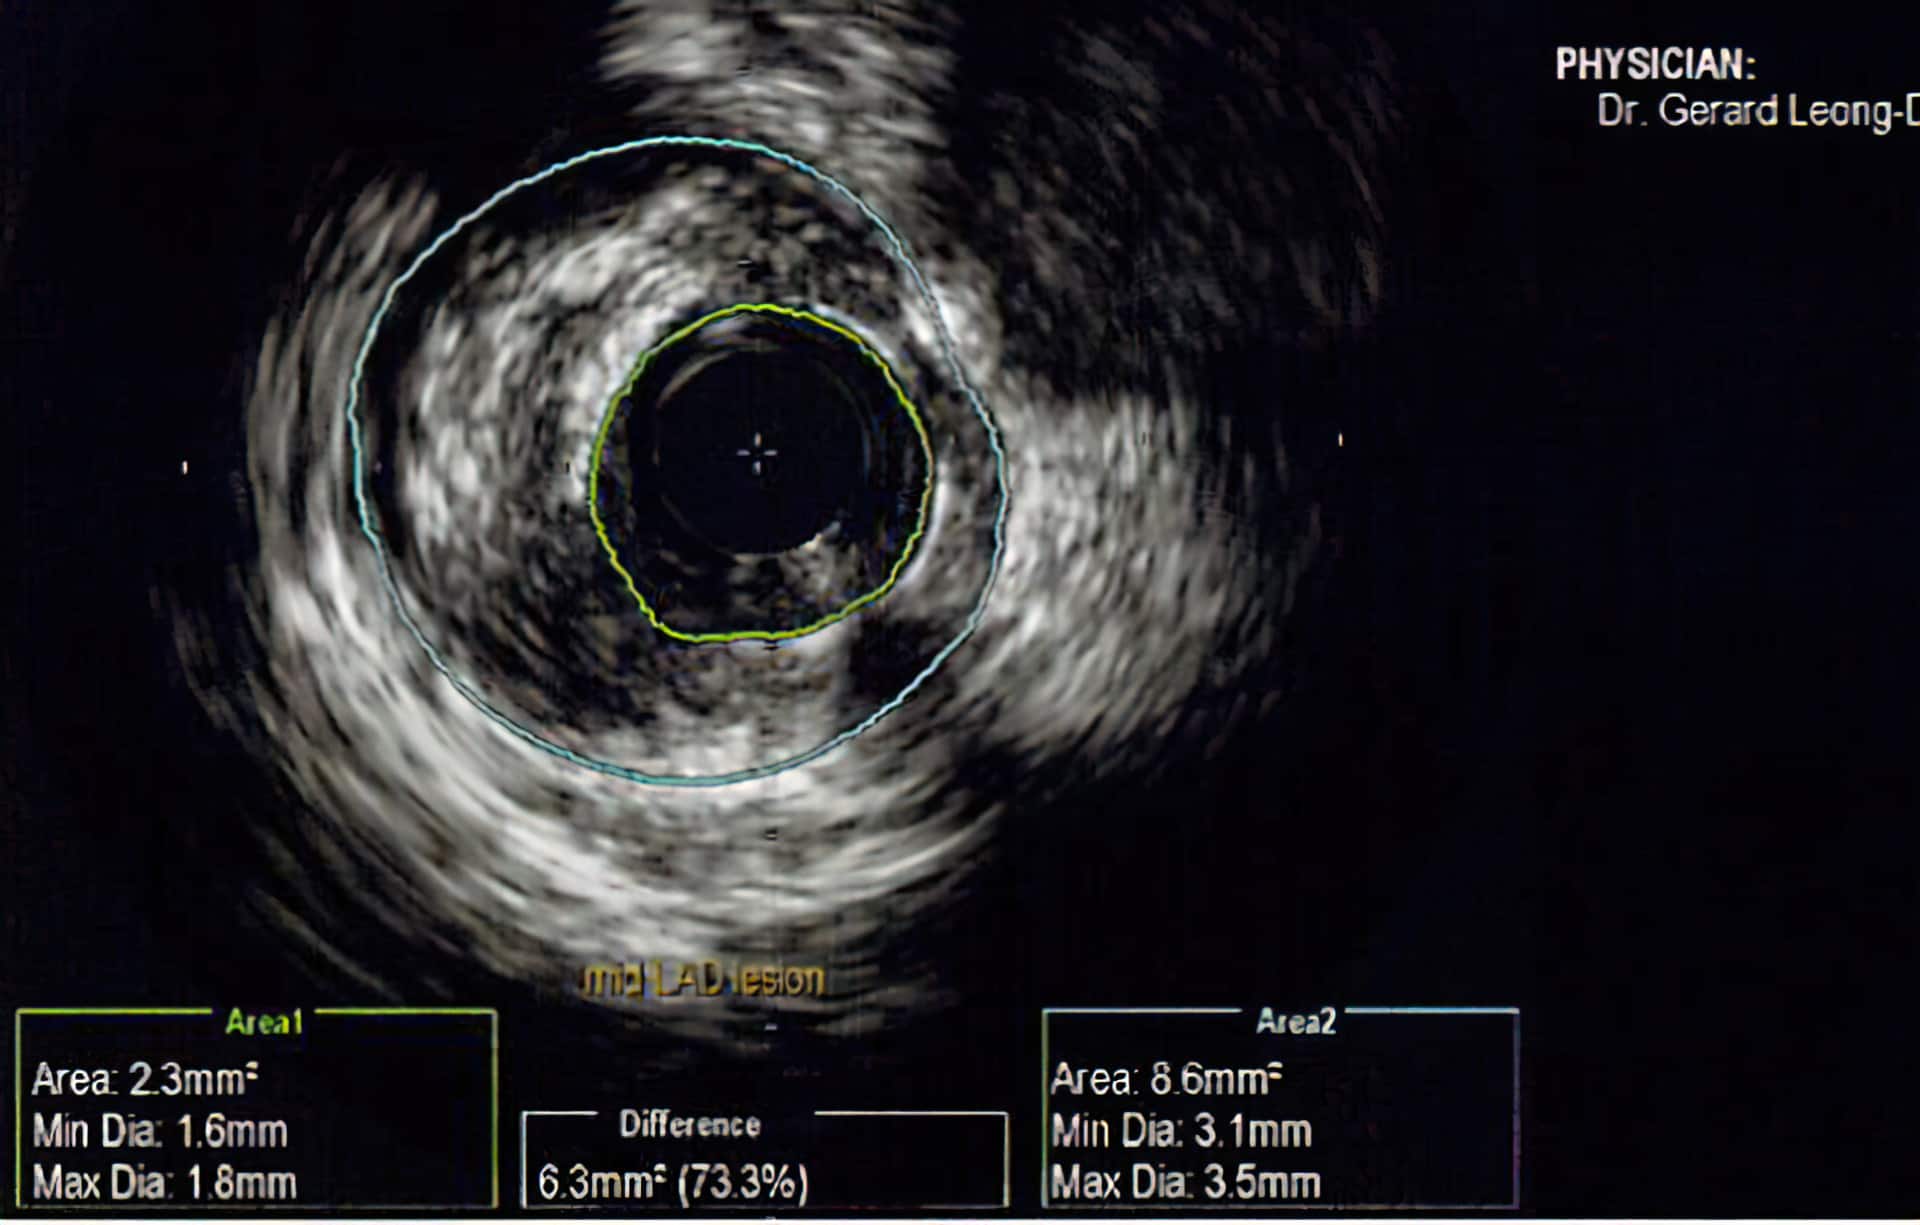

Modalitas tambahan yang dapat digunakan untuk menilai arteri koroner lebih lanjut